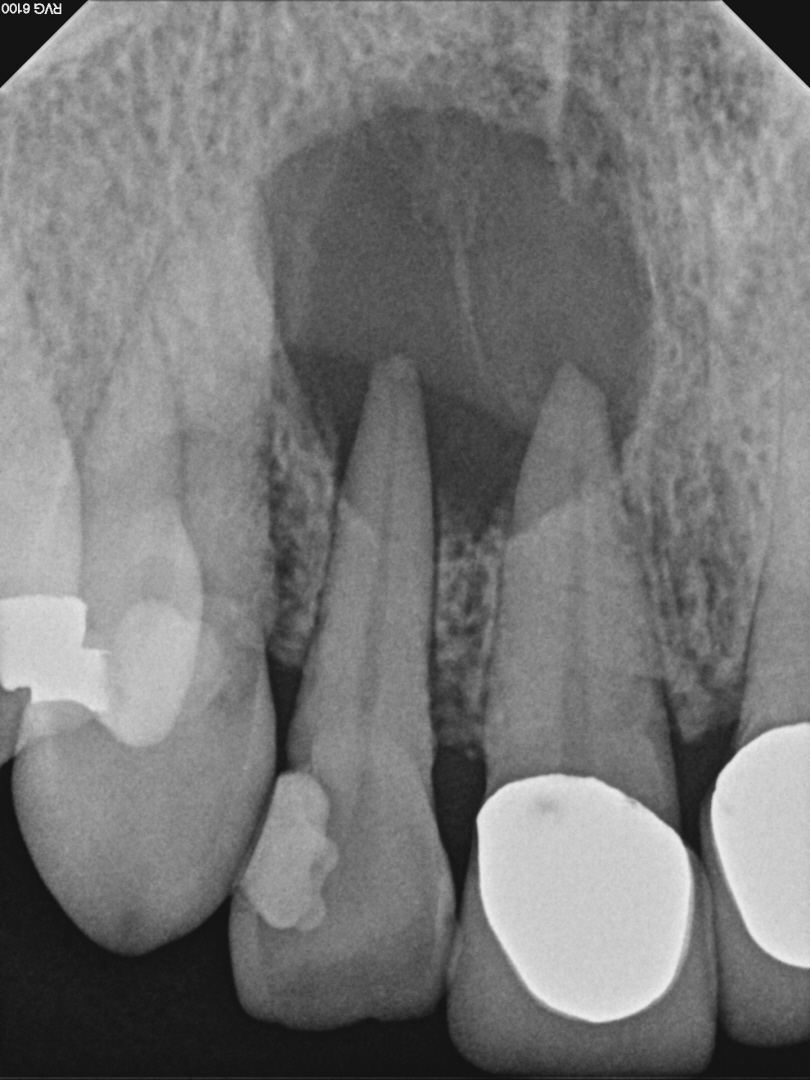

Case 5

Another case showing dramatic healing from root canal treatment. This patient had chronic sinus inflammation that never seemed to heal. The cause--an infected tooth. The top row images show both an erosion of the sinus floor from the tooth roots into the sinus cavity, as well as significant inflammation (swelling) of the sinus soft tissues that line the sinus. During retreatment I was able to find and clean all the canals, including one canal that was previously missed during the first root canal (I did not treat the original root canal). The bottom row images (one year later) shows complete re-establishment of the sinus floor (the bone that separates the sinus from the teeth) and complete resolution of the sinus swelling. There is no more infection. This retreatment case shows that even if a root canal treatment has failed, it can still often be saved. Always seek evaluation from an Endodontist before pulling out a "failing root canal"!